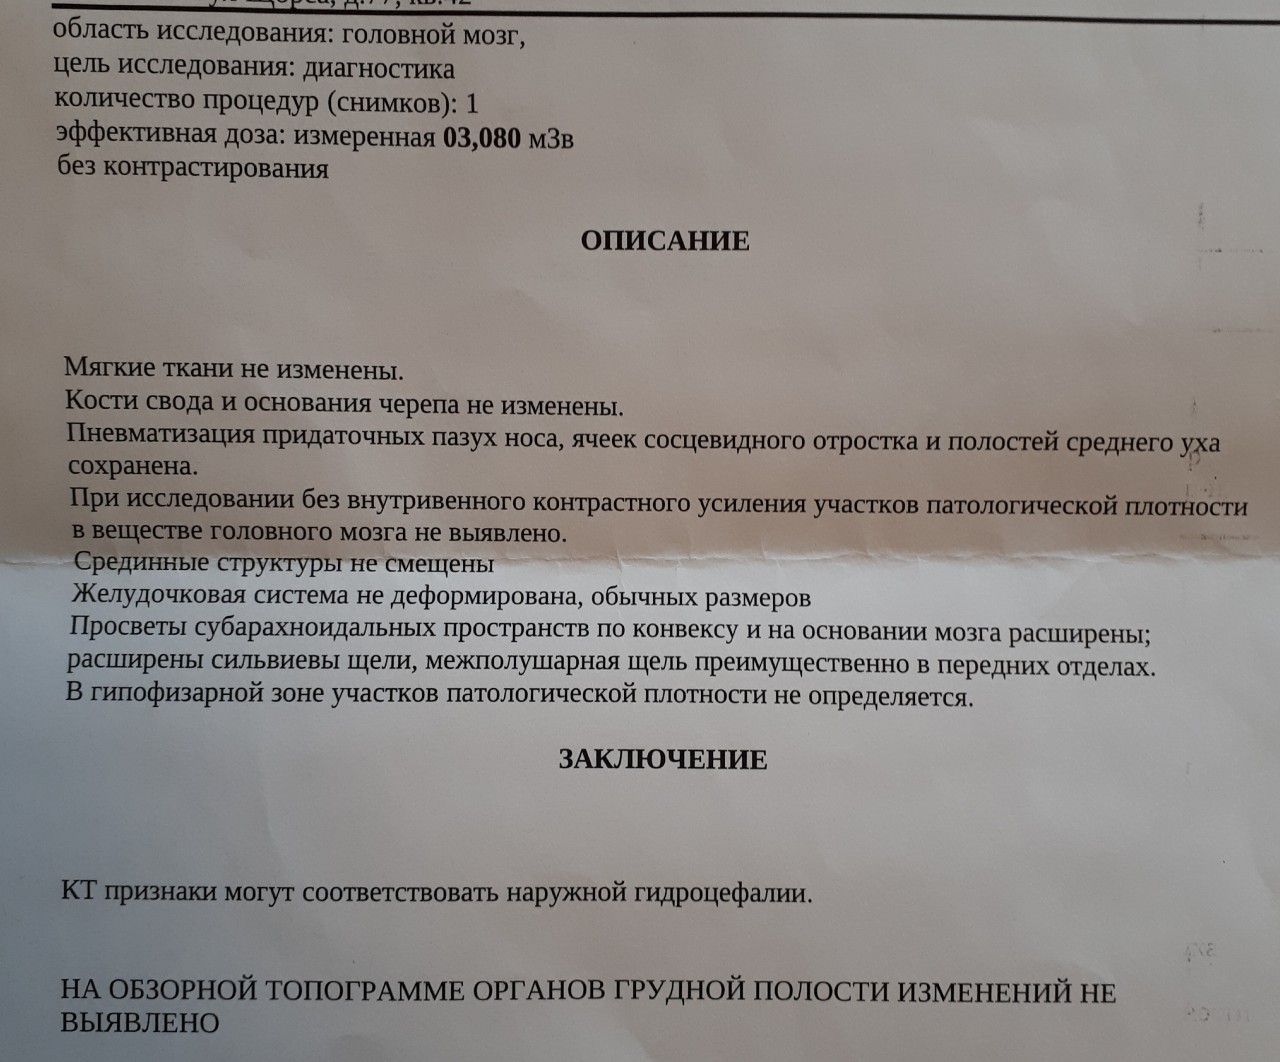

Признаки умеренно выраженной наружная

Признаки умеренно выраженной наружная 113 фото